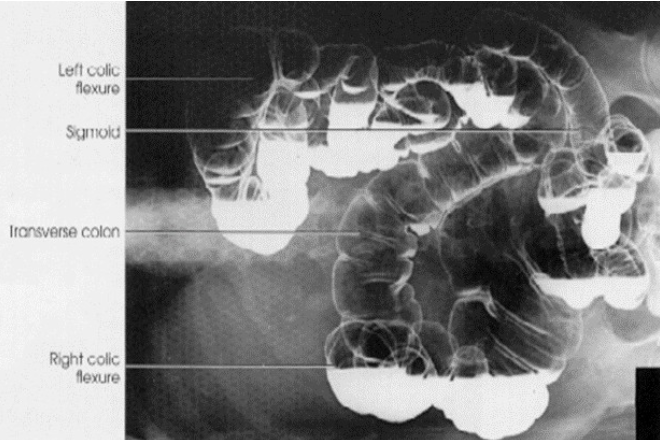

Air-Contrast Barium Enema (ACBE)

1)What does single contrast mean in the first image?

2)What does double contrast mean in the 2nd image?

3)contrast media used for this examination?

4)the 3 contraindications of the contrast used?

1)entire colon is filled only with barium sulfate (this is a BE)

2)both barium sulfate and air. (this is a ACBE)

3)Barium Sulfate

4)DON’T us if suspected bowel perforation; Bowel obstruction (high risk of retention or perforation);

Pre- or post-surgy